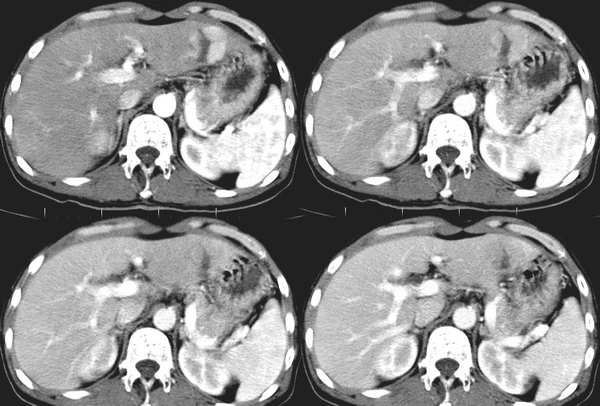

肝脏局灶性结节增生(fnh)。与肝癌鉴别点,病灶内有无强化的斑痕组织,该病例有此特点。

增强扫描病灶中央见裂隙状低密度影,支持局灶性结节状增生[emb6]

为什么不说是中心坏死?一定就是斑痕?

那位高手给解释一下动脉晚期及门脉期脾脏明显不均匀强化的原因。胰尾有问题吗!!!

病灶边缘环形增强,提示纤维包膜形成,符合肝细胞癌纤维板层型,只是未见钙化,与局灶性结节状增生实在是不好鉴别.期待病理结果.

无强化区考虑肝ca坏死,支持肝癌的诊断

考虑肝癌.因为fnh在门脉期中间疤痕组织,未见明显强化,肝癌也可能有纤维化组织.